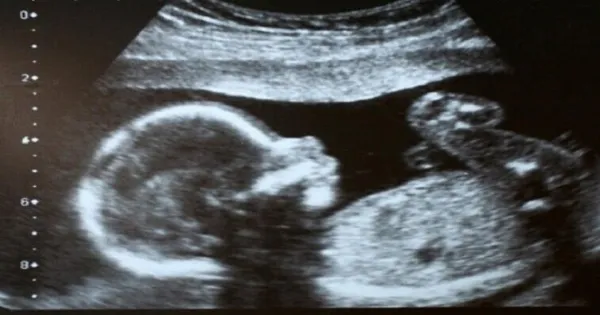

Η Έιμι Πούλ όταν ήταν έγκυος είδε το υπερηχογράφημα των 20 εβδομάδων της, και παρατήρησε ότι κάτι δεν πήγαινε καλά. Όταν είδε τη μύτη του μωρού της…έμεινε άναυδη από τον τρόμο!

Οι γιατροί επιβεβαίωσαν αργότερα, ότι ο γιος της είχε «απροσδόκητα μαλακό ιστό» που μεγάλωνε στο πρόσωπό του.